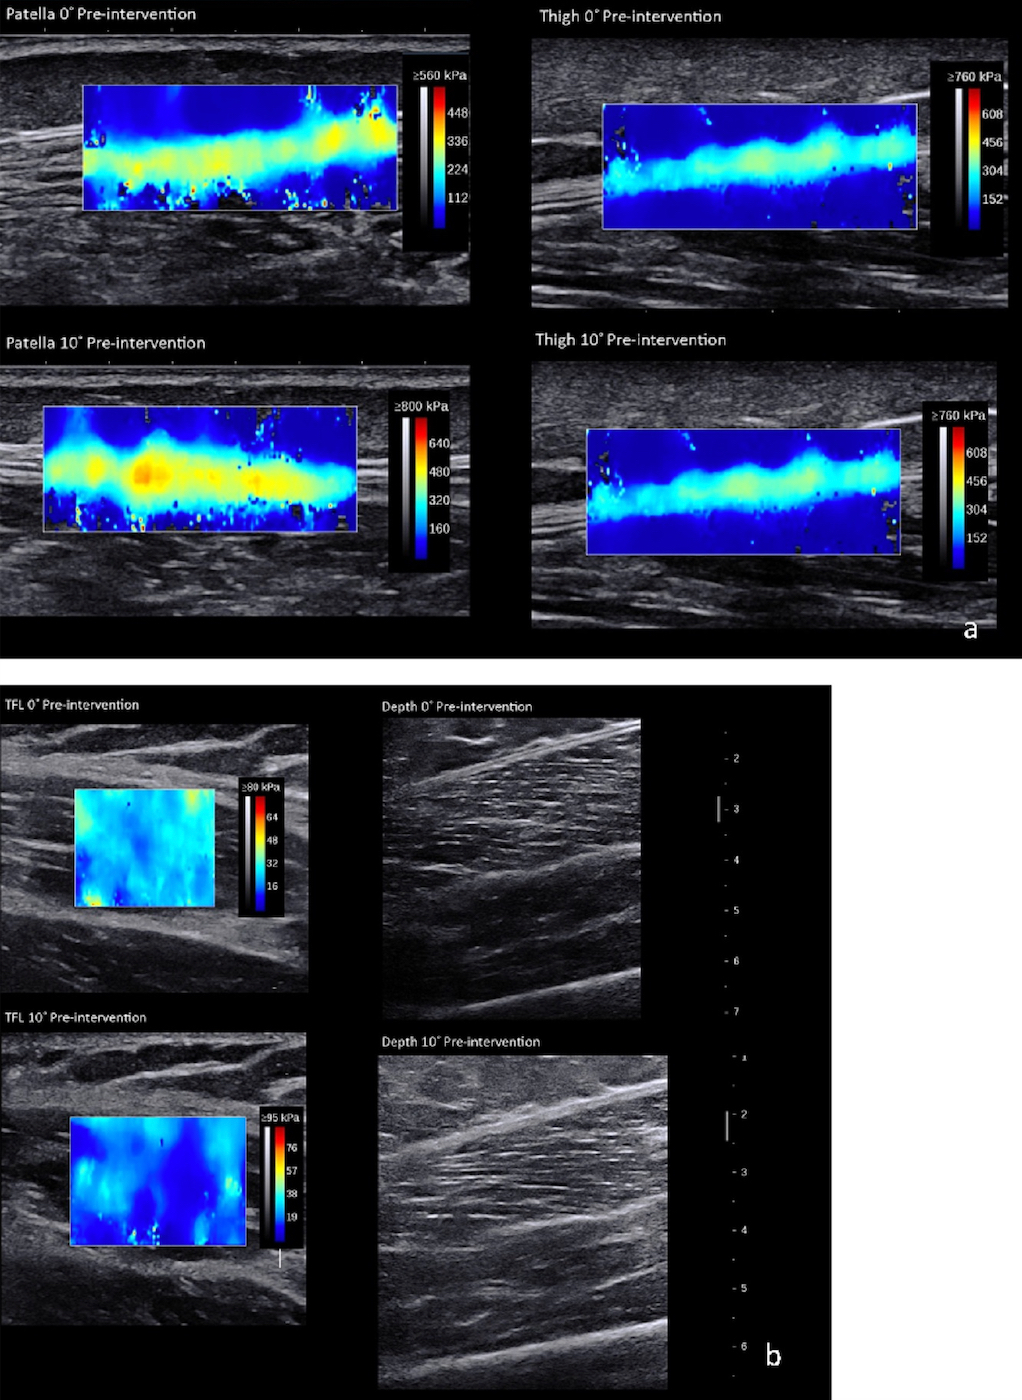

SWUE measures a soft tissue’s stiffness as Young’s modulus (kPa).39–42 Minimal detectable change for muscle and tendon tissue, respectively, is 1.72 kPa and 32.90 kPa.35,39,43–45 An Aixplorer (SuperSonic Imagine, Version 10.0, Aix-en-Provence, France) ultrasound system measured the ITB Young’s modulus at three anatomical locations: (1) lateral mid-thigh, (2) lateral thigh at the level of the patella’s superior border, and (3) TFL (Figure 2a and 2b). The two ITB points were measured with a 15-4 MHz linear transducer with the “Tendon” setting. The TFL was measured halfway between the anterior superior iliac spine (ASIS) and the femoral greater trochanter (10-2 MHz linear transducer with a “Muscle” setting). The mid-thigh location was halfway between the greater trochanter and lateral femoral epicondyle. The transducer was placed along the long axis at each location.